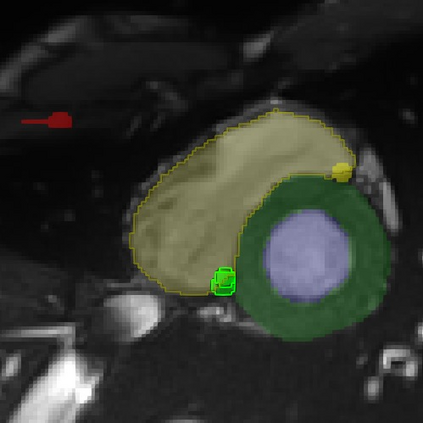

Cardiac Magnetic Resonance (CMR) images are widely used for cardiac diagnosis and ventricular assessment. Extracting specific landmarks like the right ventricular insertion points is of importance for spatial alignment and 3D modeling. The automatic detection of such landmarks has been tackled by multiple groups using Deep Learning, but relatively little attention has been paid to the failure cases of evaluation metrics in this field. In this work, we extended the public ACDC dataset with additional labels of the right ventricular insertion points and compare different variants of a heatmap-based landmark detection pipeline. In this comparison, we demonstrate very likely pitfalls of apparently simple detection and localisation metrics which highlights the importance of a clear detection strategy and the definition of an upper limit for localisation-based metrics. Our preliminary results indicate that a combination of different metrics is necessary, as they yield different winners for method comparison. Additionally, they highlight the need of a comprehensive metric description and evaluation standardisation, especially for the error cases where no metrics could be computed or where no lower/upper boundary of a metric exists. Code and labels: https://github.com/Cardio-AI/rvip_landmark_detection